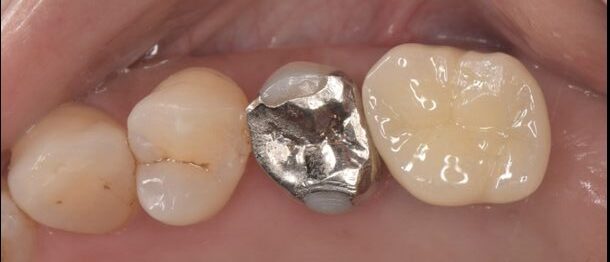

After

2ヶ月半後にセラミックのSET

インプラント埋入から2ヶ月半で治療は終了です。